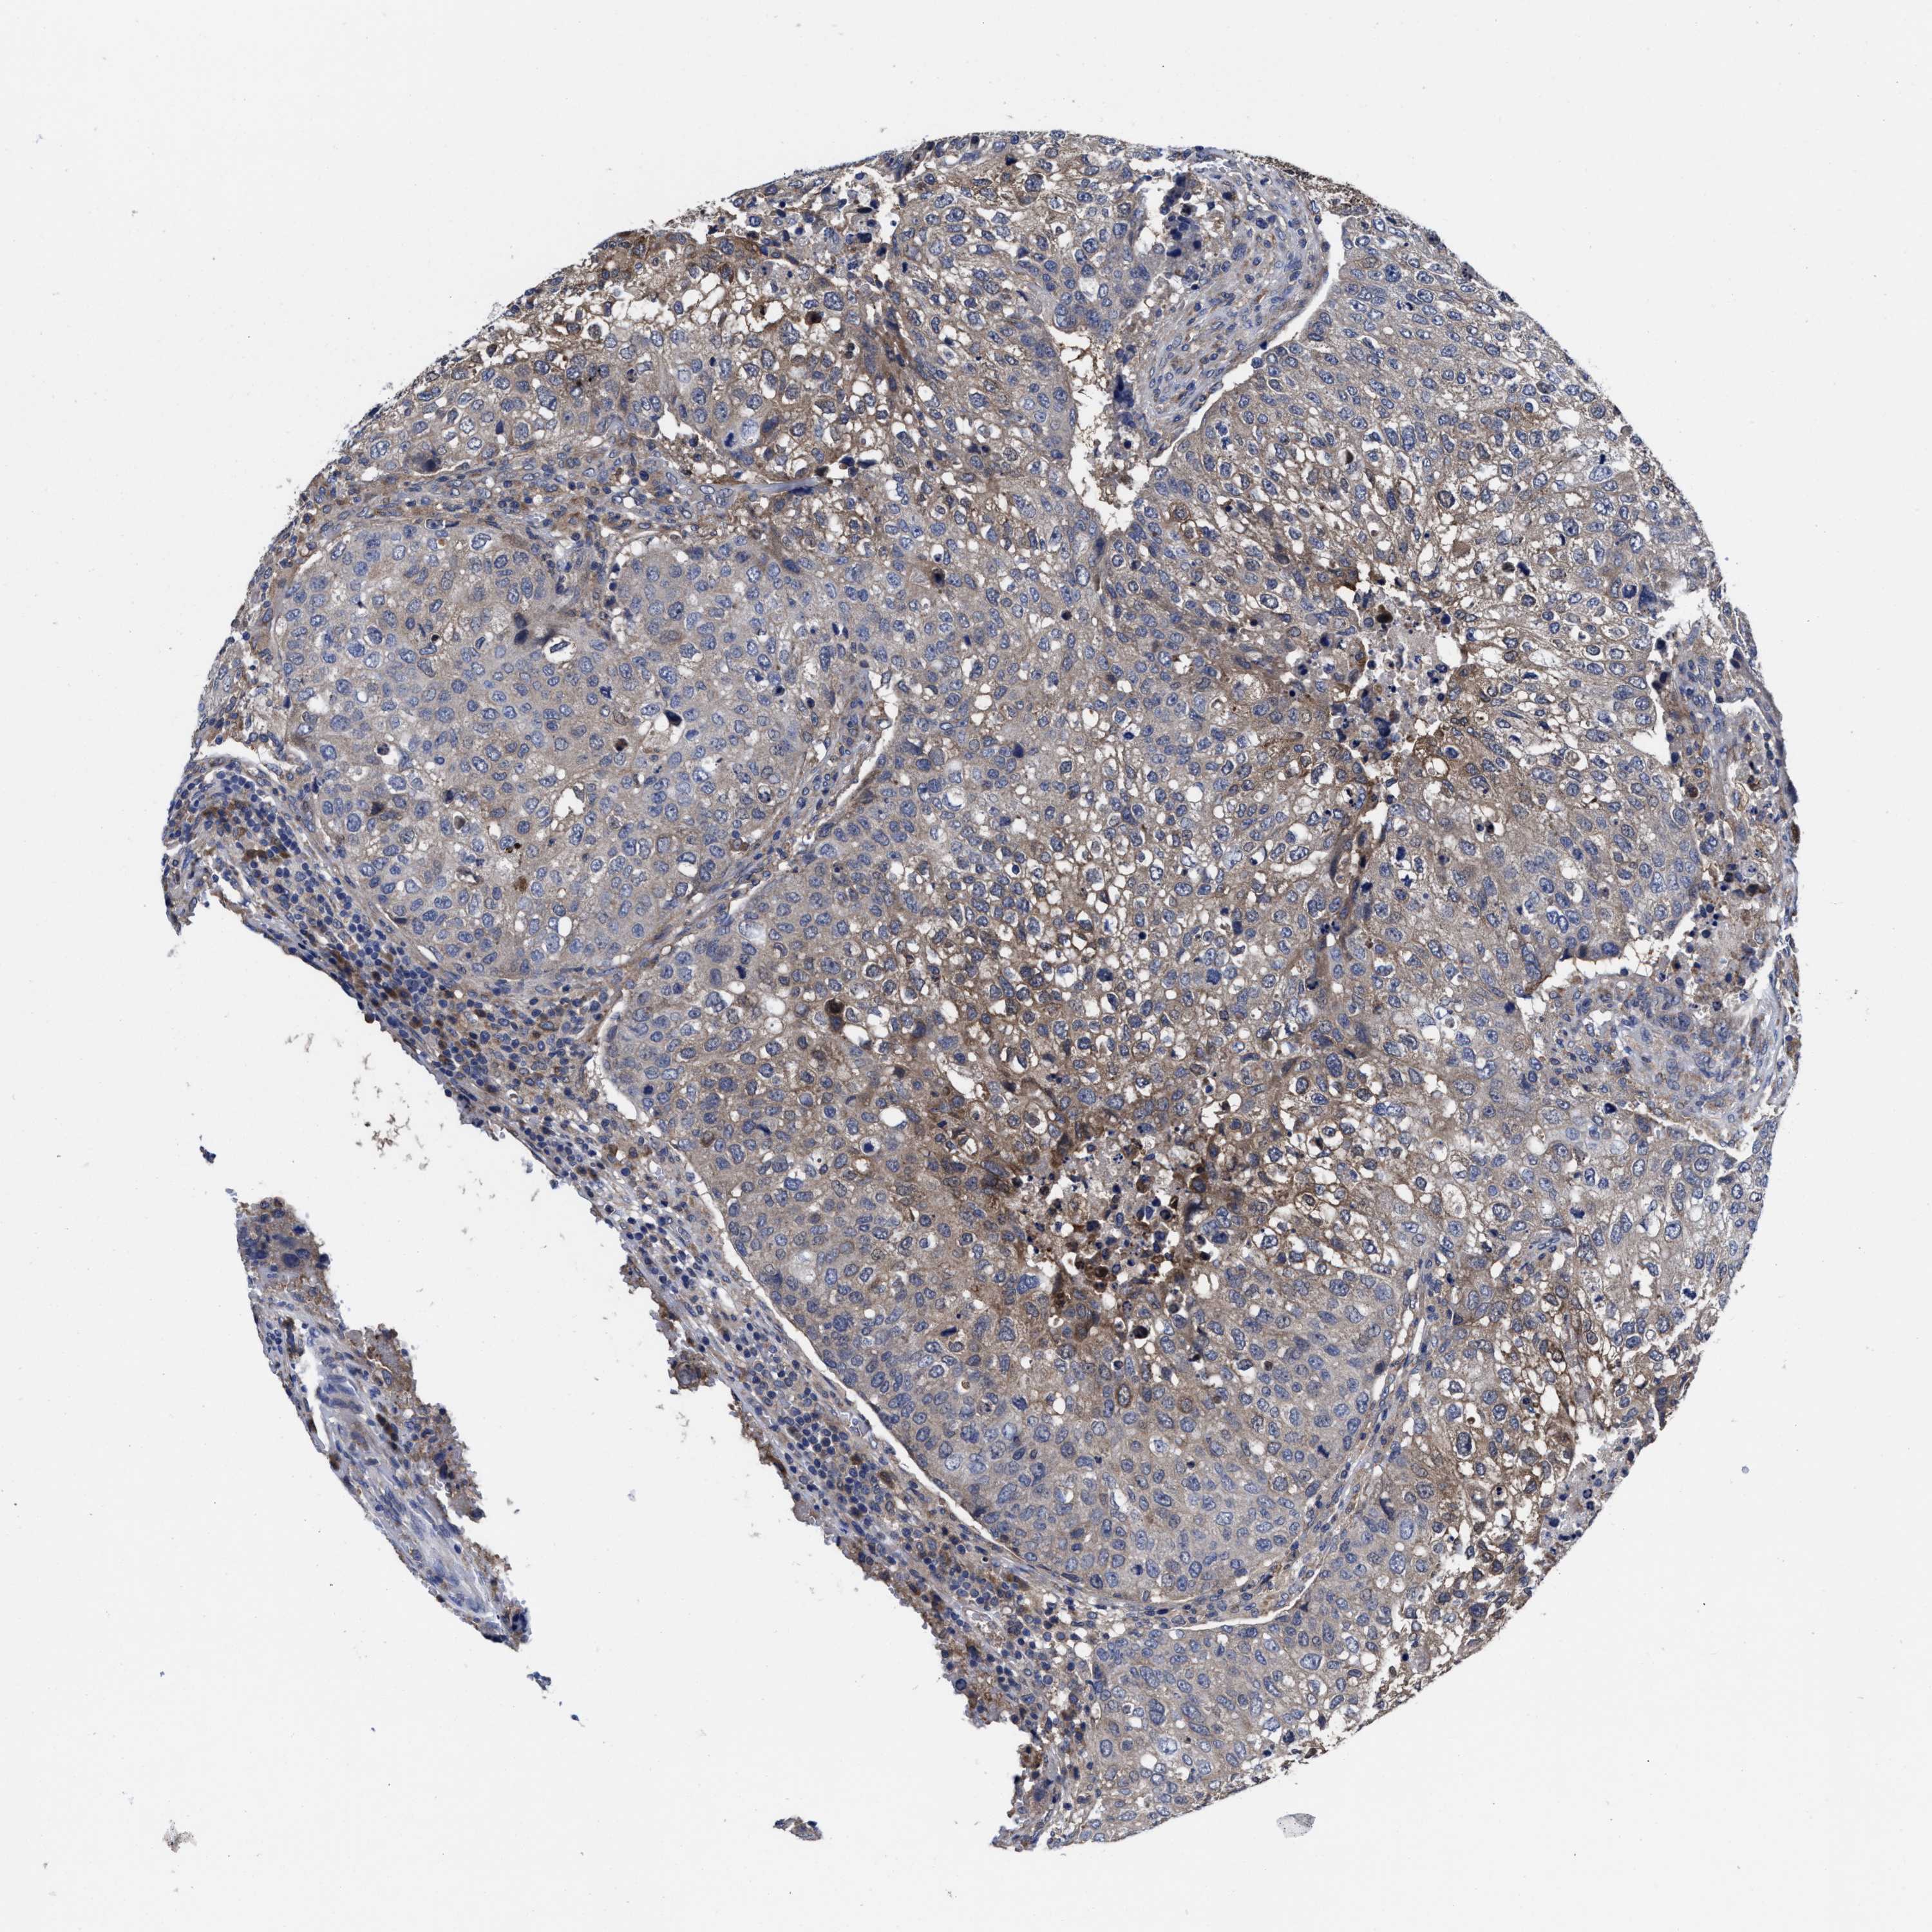

UROTHELIAL CANCER - Protein expressioni

A mouse-over function shows sample information and annotation data. Click on an image to view it in a full screen mode. Samples can be filtered based on level of antibody staining by selecting one or several of the following categories: high, medium, low and not detected. The assay and annotation is described here.

Antibody stainingi

Antibody staining in the annotated cell types in the current human tissue is reported as not detected, low, medium, or high, based on conventional immunohistochemistry profiling in selected tissues. This score is based on the combination of the staining intensity and fraction of stained cells.

Each image is clickable and will lead to virtual microscopy that enables deeper exploration of all samples and also displays staining intensity scores, fraction scores and subcellular localization as well as patient and tissue information for each sample.

Antibody HPA022931

Staining

High

Medium

Low

Not detected

Intensity

Strong

Moderate

Weak

Negative

Quantity

>75%

75%-25%

<25%

None

Location

Nuclear

Cytoplasmic/membranous

Cytoplasmic/membranous,nuclear

Urothelial carcinoma, Low grade

Urothelial carcinoma, High grade